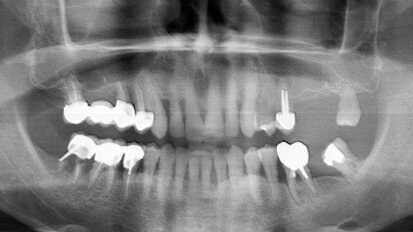

Rehabilitace Straumann